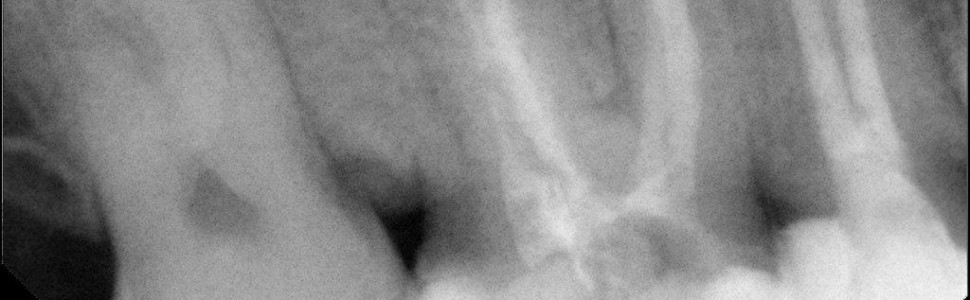

Różnorodność budowy systemu kanałowego jest spotykana weɸwszystkich grupach zębów. Znajomość anatomii oraz odchyleń od norm jest pomocna w celu uzyskania przewidywalnych rezultatów leczenia endodontycznego. Skomplikowana anatomia systemu kanałowego utrudnia jego diagnostykę, prawidłowe opracowanie wszystkich kanałów oraz ich wypełnienie. W artykule zaprezentowano przypadek leczenia pierwszego stałego zęba trzonowego szczęki z pięcioma kanałami korzeniowymi, w tym z dwoma kanałami podniebiennymi.

The variety of structure of the root canal system is found in all groups of teeth. Knowledge of anatomy and abnormalities is helpful for predictable endodontic treatment results. The complicated anatomy of the root canal system makes it difficult to diagnose, properly prepare all canals and fill them. The article presents a case of treatment of the maxillary first permanent molar with five root canals, including two palatal canals.